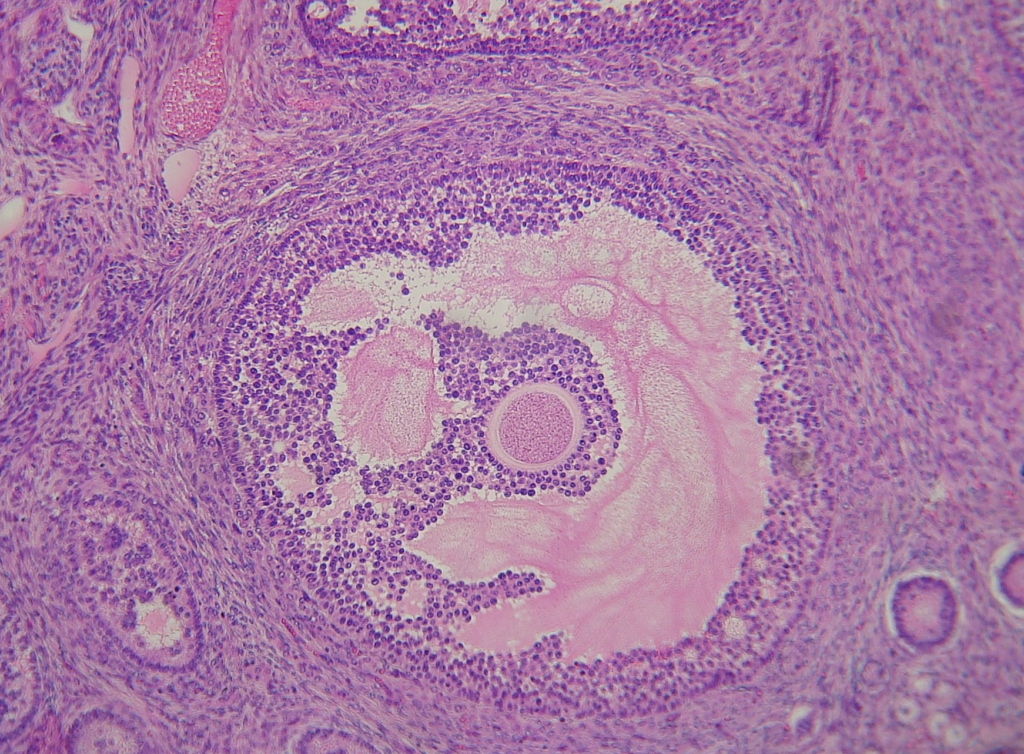

Photographie d’un follicule (ovule + cellules le protégeant) observé au microscope optique au grossissement x10x10

Source : https://www.incertae-sedis.fr/gl/docut339_54_ovaire_lames.htm